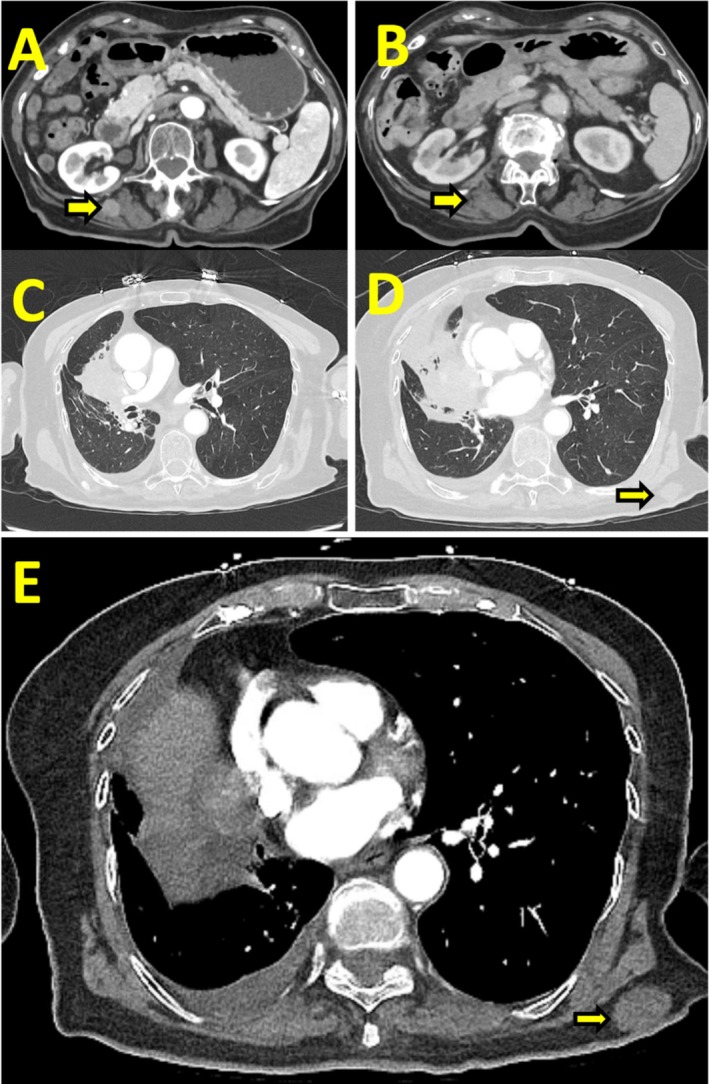

原发性肺平滑肌肉瘤是一种极为罕见的恶性肿瘤,占所有肺癌的不到0.5%。由于罕见,没有标准化的治疗指南。在被认为不能切除的病例中,预后尤其差。我们描述的情况下,一个90岁的妇女谁提出了进行性呼吸困难和咳嗽超过1个月。胸部计算机断层扫描显示一个大的右肺门肿块,延伸到右上叶和中叶,毗邻纵隔和心包膜。组织病理学分析证实为原发性肺平滑肌肉瘤。考虑到她的高龄和合并症,她不适合手术治疗。分子分析显示PDL1表达

Primary pulmonary leiomyosarcoma is an exceedingly rare malignancy, comprising less than 0.5% of all lung cancers. Due to its rarity, no standardised treatment guidelines exist. Prognosis is especially poor in cases which are deemed unresectable. We describe the case of a 90-year-old woman who presented with progressive dyspnea and cough over 1 month. Chest computed tomography revealed a large right hilar mass extending into the right upper and middle lobes, abutting the mediastinum and pericardium. Histopathological analysis confirmed primary pulmonary leiomyosarcoma. Given her advanced age and comorbidities, she was not a candidate for surgical intervention. Molecular profiling demonstrated PDL1 expression < 1% and no targetable mutations, ruling out the option of immunotherapy. She was managed with palliative radiotherapy followed by pazopanib therapy. Serial imaging demonstrated disease control, with an extended survival of approximately 5 years. Despite a median reported survival of 14 months, our patient achieved prolonged survival, highlighting the importance of an individualised therapeutic approach for elderly patients with rare malignancies.